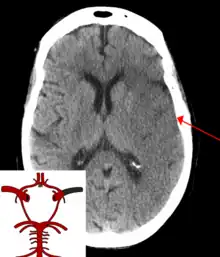

A CT showing early signs of a middle cerebral artery stroke with loss of definition of the gyri and grey white boundary

Dens media sign in a patient with middle cerebral artery infarction shown on the left. Right image after 7 hours.

Stroke is diagnosed through several techniques: a neurological examination (such as the NIHSS), CT scans (most often without contrast enhancements) or MRI scans, Doppler ultrasound, and arteriography. The diagnosis of stroke itself is clinical, with assistance from the imaging techniques. Imaging techniques also assist in determining the subtypes and cause of stroke. There is yet no commonly used blood test for the stroke diagnosis itself, though blood tests may be of help in finding out the likely cause of stroke.[63]

CT scans may not detect an ischemic stroke, especially if it is small, of recent onset, or in the brainstem or cerebellum areas. A CT scan is more to rule out certain stroke mimics and detect bleeding.[9]